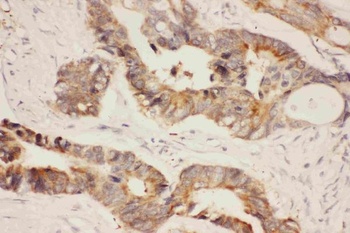

10 μg, 100 μg - Anti-DR5/TNFRSF10B Antibody [orb389514]

FC, IHC, WB

Human, Mouse, Rat

Rabbit

Polyclonal

Unconjugated

10 μg, 100 μg - Anti-Annexin IV/ANXA4 Antibody [orb18546]